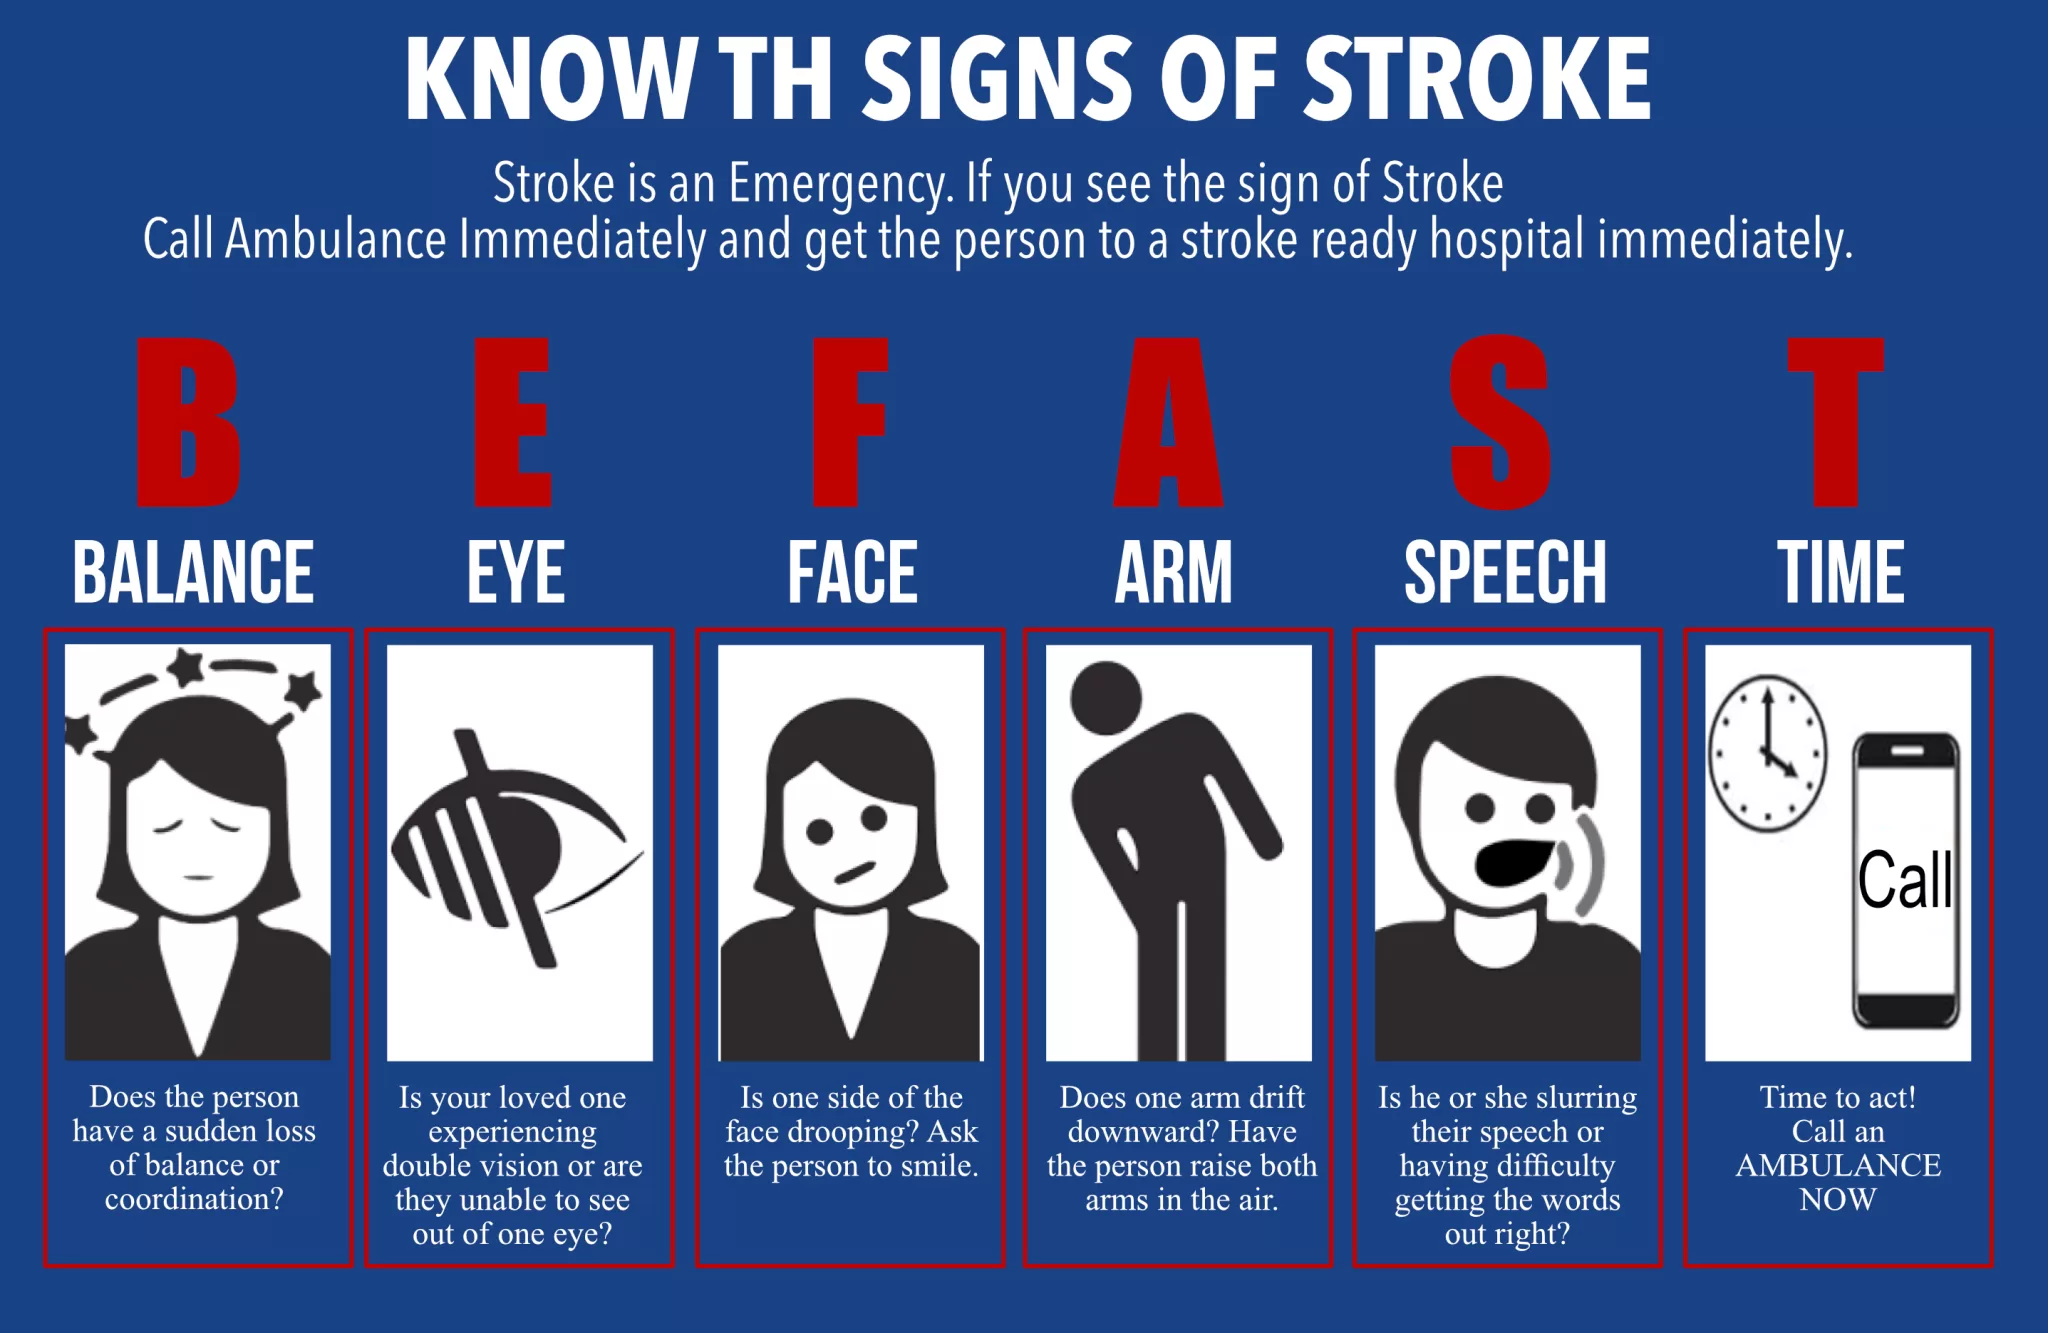

Recognizing Stroke Symptoms — BE FAST

Quick recognition of stroke symptoms can save lives. Remember the acronym BE FAST for early response.

- B – Balance loss or dizziness

- E – Eyes blurred or double vision

- F – Face drooping

- A – Arm weakness or numbness

- S – Speech difficulty

- T – Time to act – seek emergency help immediately